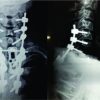

A 62-year-old man injured his right thigh by falling down from a height of around 10–12 feet on a wooden log. He developed pain and swelling over the right thigh within an hour for which he was taken to the local hospital. He was treated with injectable analgesics and discharged after few hours prescribing some oral analgesics and anti-inflammatory drugs. After reaching home, the severity of the pain gradually increased with associated numbness in the leg which was not responding to analgesic and anti-inflammatory drugs. On the next day, he visited the same hospital, the treating doctor again gave him parenteral analgesic, even then the pain did not subside and hence, they referred him to our hospital. The patient presented to us exactly 24 h after his injury. He complained of severe pain and swelling over the right thigh with loss of sensation and inability to move his affected limb which was gradually progressive and did not subside with any kind of analgesics or anti-inflammatory. In the course of the 24 h of the injury, the patient normally passed stool and urine. The patient had no significant history of illness. The patient had no history of any clotting disorder and neither of his family had suffered from any kind of bleeding diathesis. The patient neither had given any history of anti-coagulant use nor any significant drug intake. On examination, the patient was alert, conscious, and well oriented to time place and person. His blood pressure was recorded to be 148/90 mm of mercury and pulse rate of 100 per minute. On inspection, the affected thigh was grossly swollen and the overlying skin was shiny and the attitude of his hip and knee was mildly flexed. There was an ecchymosis of size around 10 × 6 cm2 over the anterolateral aspect of the thigh. On palpation, the thigh was severely tense and there was severe pain on attempted passive flexion and extension of the knee. There were no abnormal mobility and no bony crepitus in the affected limb, and the patient was able to do active straight leg raising. The affected limb was cold distal to the thigh compared to the opposite normal limb. There was lack of sensation below the knee and there was no motor activity distally. Distal pulse in the affected limb was feeble and distal SpO2 was fluctuating. Plain radiograph of the femur did not show any evidence of bony abnormality or fracture. USG color Doppler of the right lower limb showed gross collection in the anterior compartment of the thigh, subcutaneous edema, and decreased (monophasic) flow in the distal part of the femoral artery till the dorsalis pedis artery. Therefore, on the basis of the classical signs (six P’s, i.e., pain out of proportion, pain on passive stretch, pallor, paresthesia, pulselessness/ feeble distal pulse, and paralysis distal to the injury), a clinical diagnosis of compartment syndrome of the thigh involving the anterior compartment was made. Due to the late presentation, compartmental pressure measurement, further radiological investigations such as CT angiography, magnetic resonance imaging, and CT scan of the thigh were not done to avoid further delay in the definitive procedure, that is, the fasciotomy. The patient was prepared for emergency fasciotomy with emergency pre-operative work out within 3 h of presentation to the emergency department. The patient was placed in supine position on the operating table under spinal anesthesia. Under all aseptic and antiseptic measures, proper painting with 10% povidone-iodine and proper draping was done on the involved limb. Lateral incision was given over the involved thigh. The fascia lata was incised and split with scissors parallel to the skin incision along its fibers and the muscle fascia over the vastus lateralis was exposed. As the fascia was incised, the contused and swollen vastus lateralis muscle popped out. The vastus lateralis was found to be partially avulsed from the lateral intermuscular septum, while separating the vastus lateralis by blunt dissection from the fascia lata, around one and half of the kidney tray of clotted blood was evacuated which was approximately 1100 ml in amount. The vastus lateralis was retracted anteromedially and a torn thrombosed perforator was identified and ligated. After full evacuation of the clotted blood from the anterior compartment, longitudinal incision over the lateral intermuscular septum was given to relax the posterior compartment. Medial compartment was found to be soft. Multiple small horizontal incisions were given in the divided anterior edge of the tensor fascia lata to decrease the tension in the margin of the wound. Proper irrigation with normal saline was done. Few fibers of the vastus lateralis were stitched back to the lateral intermuscular septum. The wound was left open without closing the skin and a soft dressing pad was applied. Then, the patient was shifted to the ward after getting clearance from the anesthesiologist. In the course of the hospital stay, the patient regained his normal sensation and motor power (but not up to the mark). He also regained his normal distal pulse in the affected limb on the next day of fasciotomy. In the post-operative stay, he was given broad spectrum I.V. antibiotics, subcutaneous low-molecular-weight heparin (as advised by the cardiothoracic vascular surgeon), oral analgesic, oral anti-inflammatory, oral indomethacin to prevent heterotopic ossificans, and oral proton-pump inhibitor. After a few days of alternate day antiseptic dressings, vacuum-assisted closure (VAC) was applied to decrease the size of the wound. After 5 days of VAC treatment, the wound was inspected and found to be healthy and smaller than previous. As advised by the physiotherapist, the normal physiotherapy for the affected limb was started and he was given a foot drop splint for his foot drop which actually was gradually improving. The patient was shifted to the plastic surgery department in our hospital for the skin grafting on the surgical wound. Follow-up at 7 months of the injury, the patient has regained his normal muscle power and near-normal range of motion of all the joints in the affected limb.